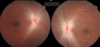

Como é a fundoscopia nas neuropatias ópticas tóxicas e medicamentosas?

Normal no início -> atrofia temporal com a cronicidade

Quais as características da neuropatia tóxica por metanol?

Edema bilateral de disco óptico

Quais os achados fundoscópicos das neuropatias ópticas carenciais?

Início - normal ou leve hiperemia

Casos crônicos - atrofia temporal